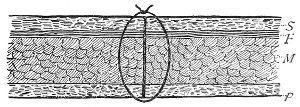

An accurate knowledge of the anatomy and mechanism of the female perineum is essential to an understanding of the nature and treatment of injuries to this structure. The anatomical structures lying between the anus behind and the symphysis pubis in front are those that most directly interest the gynecologist. Proceeding from 57 below upward, we find the following structures lying in superimposed planes: the skin, the superficial fascia, the deep layer of the superficial fascia, the transversus perinæi and the sphincter vaginæ muscles, the anterior layer of the triangular ligament, the posterior layer of the triangular ligament, the levator ani muscle (Fig. 19).

Fig. 19.—Dissection of female perineum: on the left side the perineal muscles are exposed by the reflection of the perineal fascia; on the right side the muscles and the superficial layer of the triangular ligament have been removed, thereby exposing the deep layer of the ligament. S. V., Sphincter vaginæ muscle.

Fig. 22.—Sagittal section showing relations of the several layers of fascia within the pelvic floor (Dickinson).

The vagina extends, as a transverse slit in the pelvic floor, upward and backward, approximately in the direction 60 of a line drawn from the ostium vaginæ to the fifth sacral vertebra. It is approximately parallel with the conjugate of the brim, so that when the woman is erect the long axis of the vagina is inclined at an angle of 60° to the horizon. The vagina is not a vertical open tube: it is a slit in the pelvic floor, in health always closed by the accurate apposition of the anterior and posterior walls (Fig. 21). The anterior vaginal wall is about 2½ inches long in a vertical mesial line. The posterior vaginal wall is about 3½ inches long. The vaginal walls are triangular in shape, being broader above than below. The shape of the normal vagina at the pelvic outlet is shown by Fig. 23. The section here shows the vaginal 61 slit of the shape of the letter H. The portions of the slit extending backward and somewhat outward are called the vaginal sulci or furrows. They are directions of diminished resistance in which tears are liable to occur.